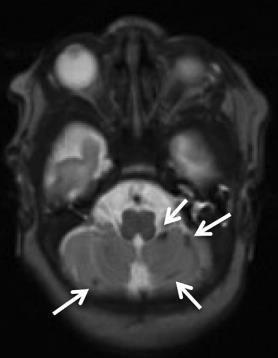

Germinal matrix-intraventricular haemorrhage (GMH-IVH)

Focal infarction

White matter injury

Global injury from hypoxic-ischaemic encephalopathy (HIE)

The study of brain connectivity can produce biomarkers of damage and functional recovery in Cerebral Palsy (CP).

Patients with spastic and dystonic CP have different structural connectivity maps.

Patients with CP show different motor functional connectivity maps, with reduced interthalamic connectivity.